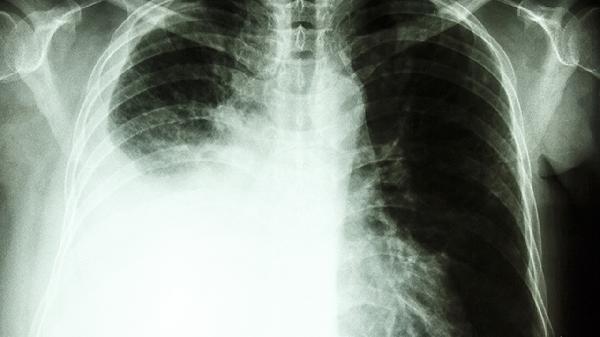

4、肺癌:痰中带血丝可能是肺癌的早期症状,尤其是长期吸烟者。诊断需结合胸部CT、支气管镜等检查。治疗包括手术切除、放疗、化疗及靶向治疗,早期发现预后较好。